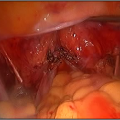

How are Hysteroscopic operations performed ?

The hysteroscope allows good vision inside the uterus .The uterus is kept distended by a continuous flow of a liquid by� specialised pressure-controllong device. Specialised fine electrosurgical tools are passed into the cavity under vision and the pathology is tackled. The patient goes home the same day.